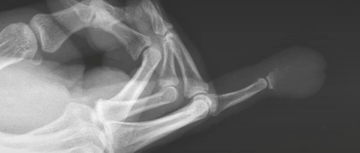

骨肿瘤样病变——表皮样囊肿

#表皮样囊肿

2026.03.22

447浏览